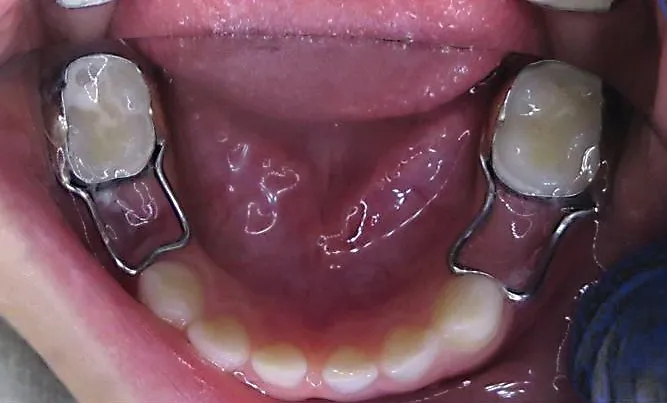

Rola retencji: czy po usunięciu ósemki potrzebny jest aparat retencyjny?

Jeśli ekstrakcja ósemek była częścią leczenia ortodontycznego, to po jego zakończeniu aparat retencyjny jest absolutnie kluczowy. Jego zadaniem jest utrzymanie zębów w nowo uzyskanej, prawidłowej pozycji i zapobieganie ich powrotowi do stanu sprzed leczenia, a także niekontrolowanym przesunięciom po usunięciu ósemek. Nawet jeśli nie miałeś leczenia ortodontycznego, w niektórych przypadkach, zwłaszcza przy ryzyku powstawania luk, stomatolog może rozważyć zastosowanie tymczasowej retencji, aby ustabilizować zgryz.